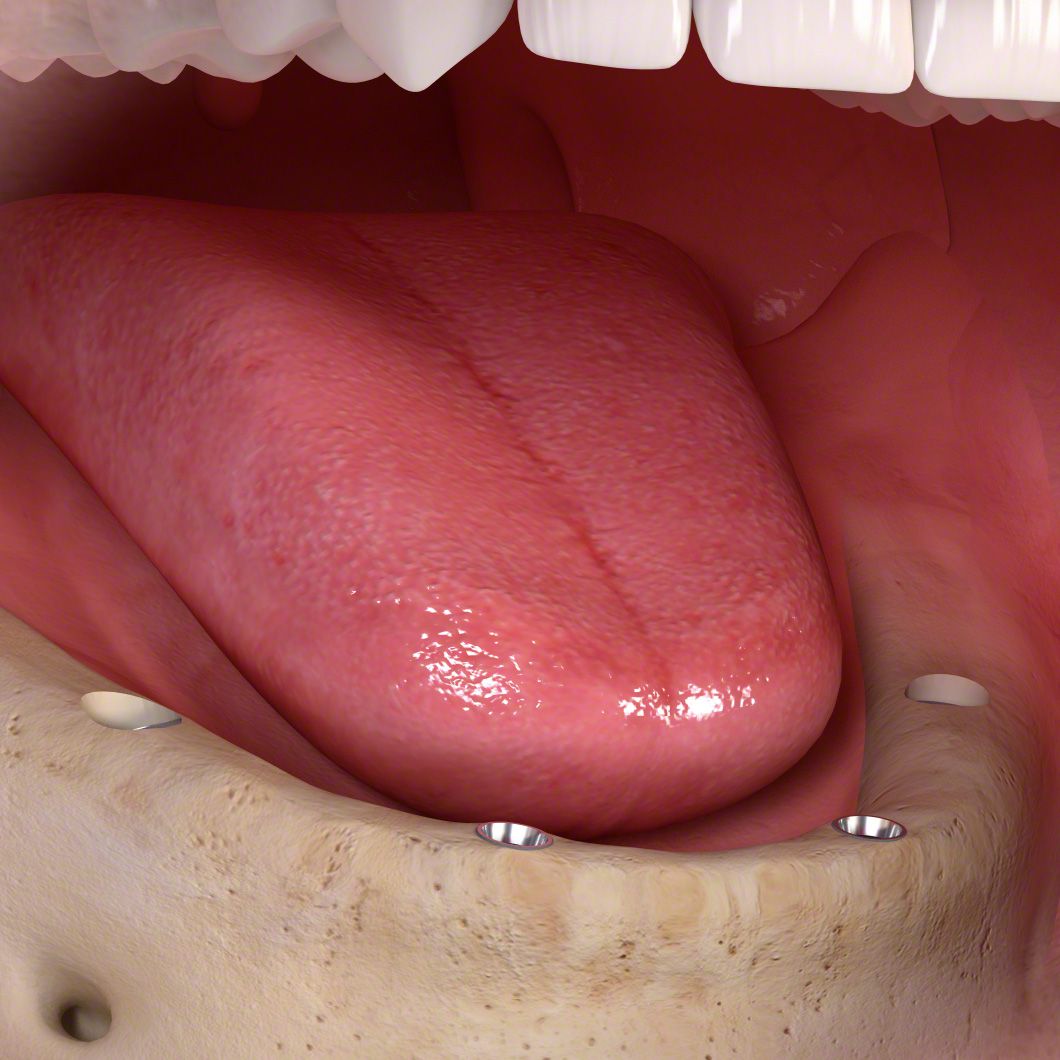

Die entstandene Lücke kann mit einer künstlichen Zahnwurzel, d.h. mit einem Implantat geschlossen werden. Implantate, meist aus Titan oder Keramik, werden dabei in einem kleinen chirurgischen Eingriff in den Kieferknochen eingesetzt. Nach dem Einheilen tragen sie später den eigentlichen Zahnersatz (Kronen, Brücken, Prothesen).